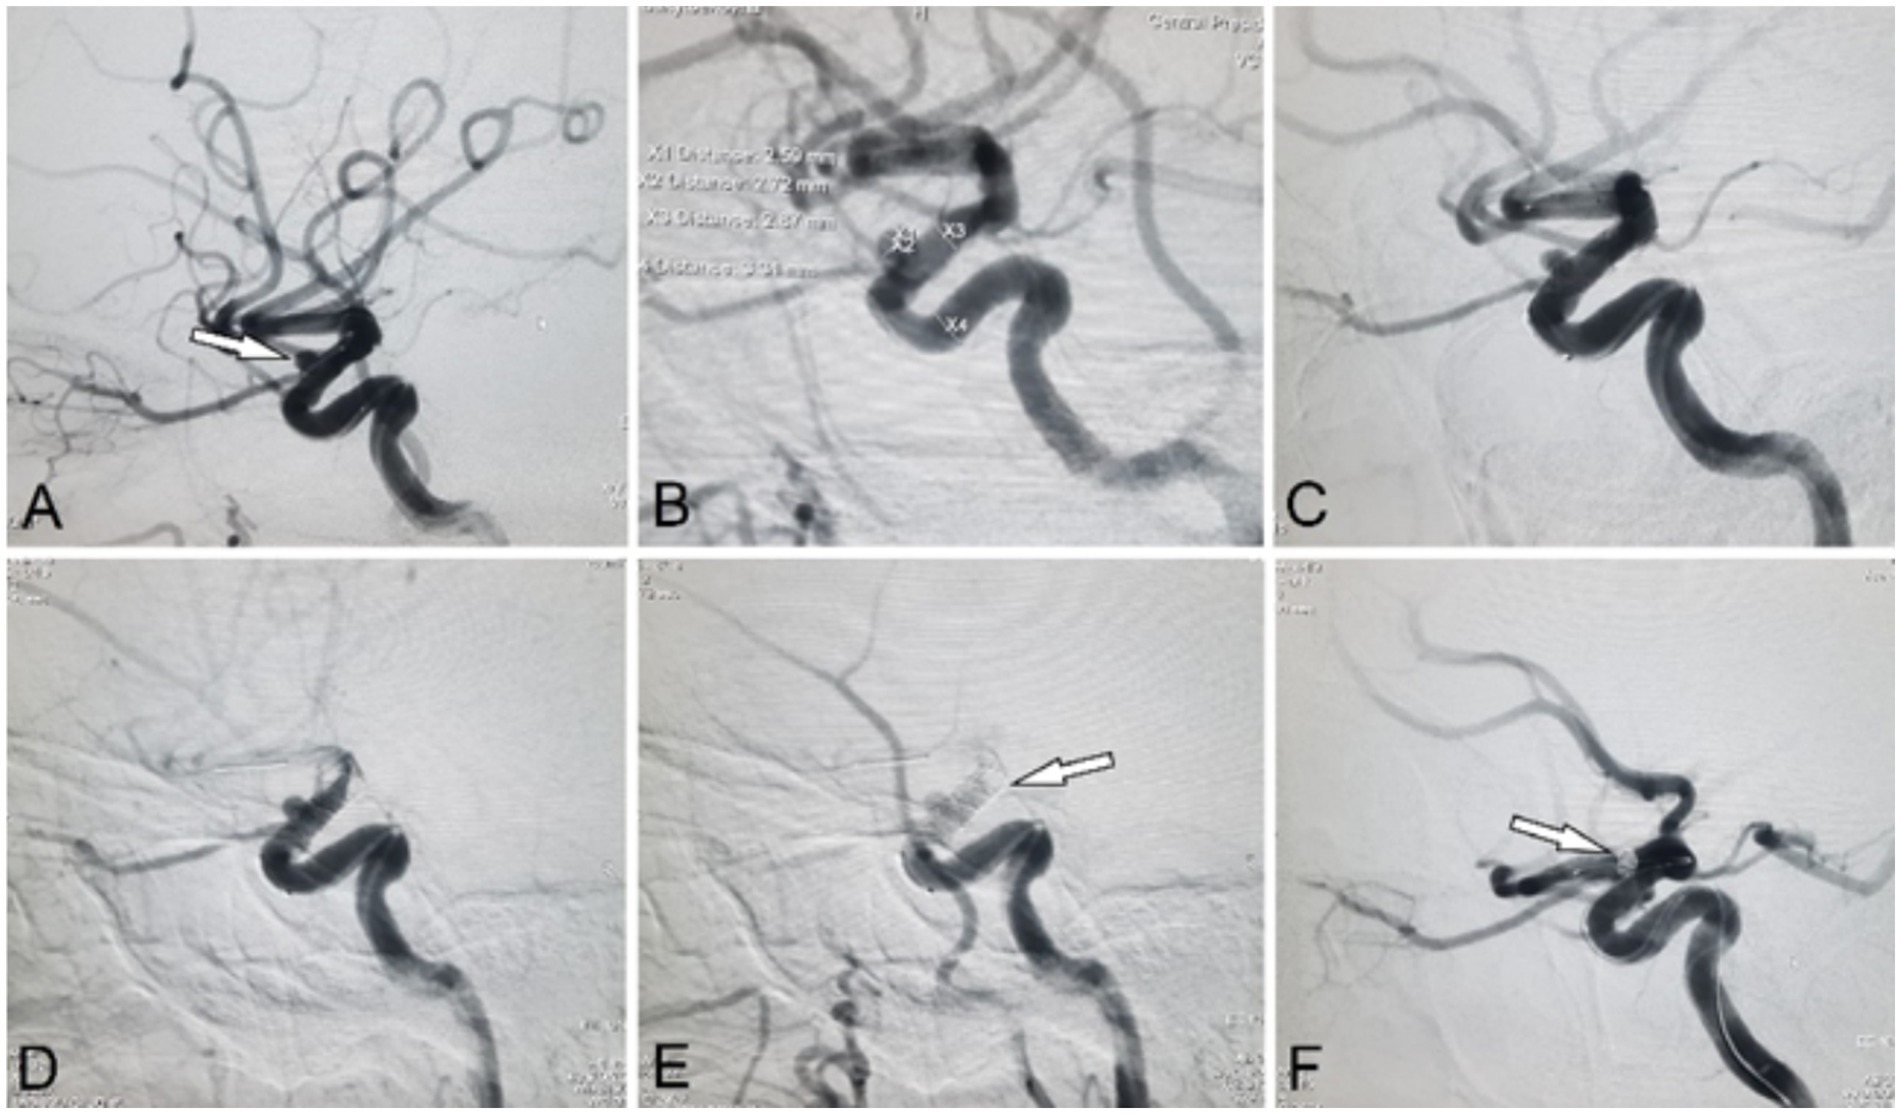

Figure 2

Representative case of a positive Kazakh ThromboTest (KTT) during an attempted internal carotid artery (ICA) stenting with a flow-diverter. (A,B) Angiographic views show a saccular aneurysm located at the C4 segment of the ICA. (C) Partial deployment of a self-expanding flow-diverter stent without full expansion. (D) Control angiography at 7 minutes post-deployment. (E) Follow-up at 14 minutes reveals a positive KTT with visible in-stent thrombosis and near-occlusion of the ICA. (F) Rescue coil embolization of the aneurysm following stent removal.